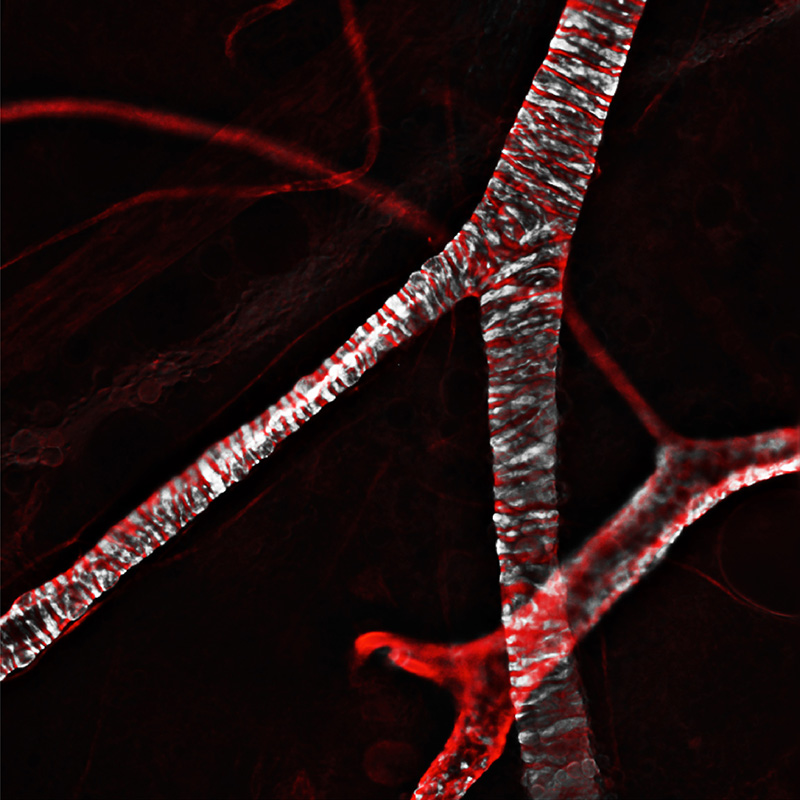

Through arteries and arterioles (foreground) the heart pumps blood throughout the body. It flows back to the heart through venules and veins. The vessels’ muscle cells (white) help to control blood pressure. Confocal fluorescence microscopy© Jacopo Di Russo, Lydia Sorokin